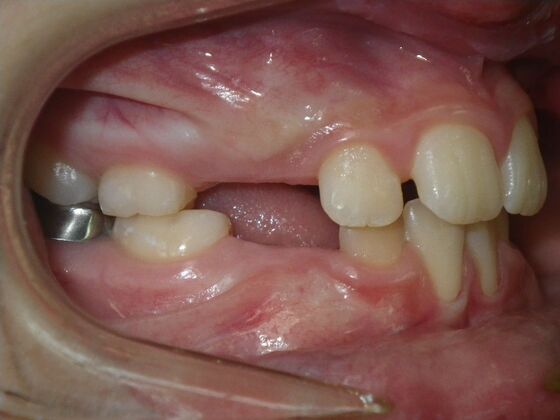

Orthodontics: Case 43

Patient presented with mixed dentition and mild deep overbite, excessive overjet,and rotated lower incisors. She also had a lower bilateral lingual retainer, preventing lower molars from coming forward. She was treated with utility archwires initially, waiting for eruption of cuspids and bicuspids. This was followed by conventional straight wire appliances and upper and lower standard hawley retainers.